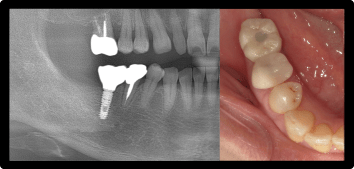

骨造成(サイナスリフト)を伴うインプラント治療

上の奥歯に歯を入れたい

BEFORE/AFTER

症例概要

年代・性別

50歳代 女性

主訴

治療内容

右上6番インプラント治療、サイナスリフト

治療期間

4ヶ月

治療のリスク

インプラント周囲炎のリスクがあるため、メンテナンスに来ていただきます。

治療費用

572,000円(税込)